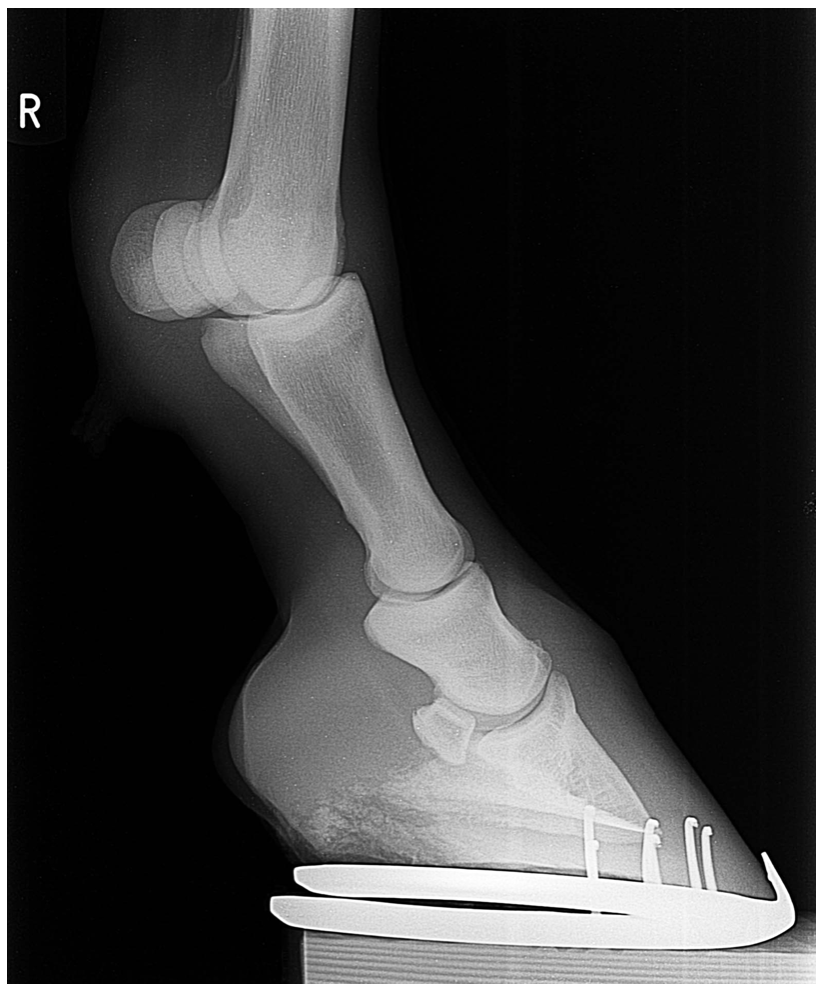

Ut fra bildene kan man bedømme bruddets type og omfang. For å bestemme skadens alvor, er røntgen det viktigste hjelpemiddelet.

Når hesten “brekker benet”, er det en av knoklene som er brukket av, helt eller delvis. Knoklene vises tydelig på røntgenbilder.

Men det finnes ulike typer bruddskader, og skadens art bestemmer den videre behandlingen og prognose.

Et brudd, eller en fraktur, er en bruddlinje som går gjennom en knokkel slik at det dannes et eller flere fragmenter.

Ved en dislokert fraktur har knokkeldelene også forskjøvet seg i forhold til hverandre. Dette er svært smertefullt, og hesten er ofte svært halt.

Et komplisert brudd betegner et brudd med mange biter. Det er da flere bruddlinjer i stedet for en, og i stedet for to store fragmenter, ses mange små, akkurat som om benvevet i området er knust.

Når en fraktur angår et ledd, vil det si at bruddlinjen strekker seg inn i et ledd og deler knokkelen i to i et område som utgjør en leddflate. Dette kan gjøre skaden mer alvorlig, fordi det vil utvikles ujevnheter i leddflaten etter hvert som bruddet leges. Et ledd er avhengig av at leddflatene glir mykt mot hverandre, og ujevnheter kan forårsake kronisk leddbetennelse.

Alt dette, samt flere andre faktorer, bedømmes ut fra røntgenbildene. Med dette som grunnlag, vurderer man neste steg.

Kirurgisk behandling innebærer operasjon. Bruddet stabiliseres ved hjelp av skruer, plater og/eller wire. Man er da ute etter å bringe bruddflatene i nær kontakt med hverandre, nøyaktig slik benet var før skaden oppstod. Noen fourtsetninger må være til stede for at dette skal la seg gjennomføre, og i blant velger kirurgen å avstå fra operasjon, fordi risikoen overstiger den sannsynlige gunstige effekten av inngrepet.